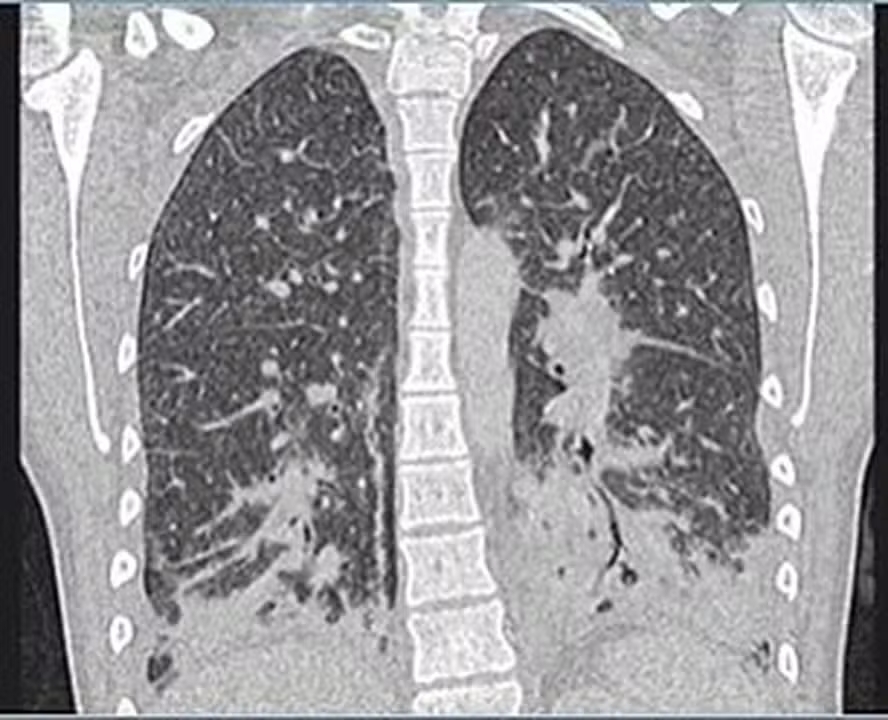

Ela foi inicialmente diagnosticada com pneumonia bacteriana grave, que foi tratada com antibióticos por cinco dias, porém, devido a não melhora dos sintomas, os médicos realizam um exame de raio-x que indicou manchas translúcidas por todos os pulmões, sugerindo que eles estavam cheios de líquido e apresentavam sinais de danos nos tecidos.

As imagens dos exames mostravam que a jovem tinha opacidades de vidro, geralmente ocorre junto com a consolidação nos pulmões. Consolidação se refere ao espessamento ou inchaço do tecido pulmonar, que acontece quando os espaços de ar nos pulmões se enchem de fluido, pus, sangue ou células.